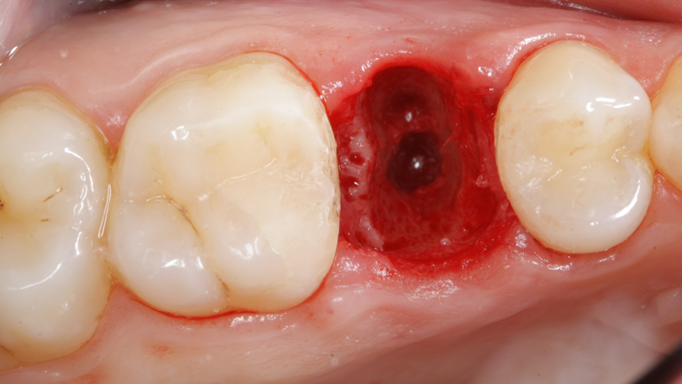

Clinical case: Extraction, immediate implant placement, & provisionalization

- Courtesy of Dr. Iulian Filipov, Romania -

Keywords

AnyRidge, R2GATE, guided surgery, immediate placement, immediate provisionalization, initial stability, Dr. Iulian Filipov, #25, maxillary posterior, immediate loading, Mega ISQ